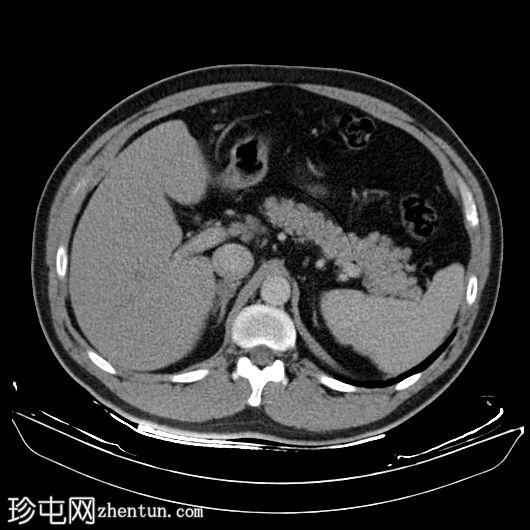

轴位

平扫

右下肺支气管内肿块较前增大,现已延伸至中间支气管,并可见对比剂强化。右下肺阻塞性肺不张。

左下肺支气管出现新的类似肿块。